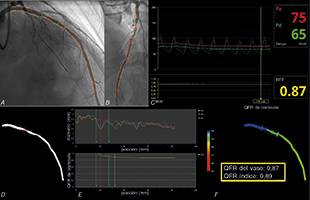

La valoración prospectiva de la correlación entre QFR y RFF se llevó a cabo en 12 pacientes (15 lesiones) de la población del estudio siguiendo el protocolo ya descrito en estudios publicados11. Las principales características de esta muestra de validación fueron similares a las de la cohorte QFR tal y como muestra la tabla 1. No hubo ninguna complicación tras el uso de las guías de presión. Los valores RFF medios fueron 0,87 ± 0,06 y la diferencia media con respecto a los valores QFR, 0,017 ± 0,02. La figura 1 muestra un ejemplo paradigmático de una lesión evaluada mediante RFF y QFR. El coeficiente de correlación interclase fue 0,959 (intervalo de confianza del 95%, 0,882-0,986). En 4 lesiones (26,7%) el análisis de la RFF se llevó a cabo durante el procedimiento índice tras la revascularización de la lesión causante. En esta muestra no se observó diferencia alguna en la precisión diagnóstica de la QFR entre el procedimiento índice y el diferido (diferencia media relativa 0,0346 ± 0,29 y 0,114 ± 0,10, p = 0,214); se utilizó el método de Bland-Altman para ver el grado de concordancia entre estas mediciones y la correlación según el procedimiento descrito en la figura 2.

Figura 1. Ejemplo representativo de concordancia entre RFF y QFR en lesión en no-ARI. A: OAD, 30o; CRA, 30o; B: OAI, 40o; CRA, 20o; C: RFF; D: reconstrucción angiográfia en 3D. E: diámetro luminal y retirada QFR; F: valores QFR. ARI: arteria no responsable del infarto; CRA: craneal; OAD: oblicua anterior derecha; OAI: oblicua anterior izquierda; QFR: ratio de flujo cuantitativo; RFF: reserva fraccional de flujo.